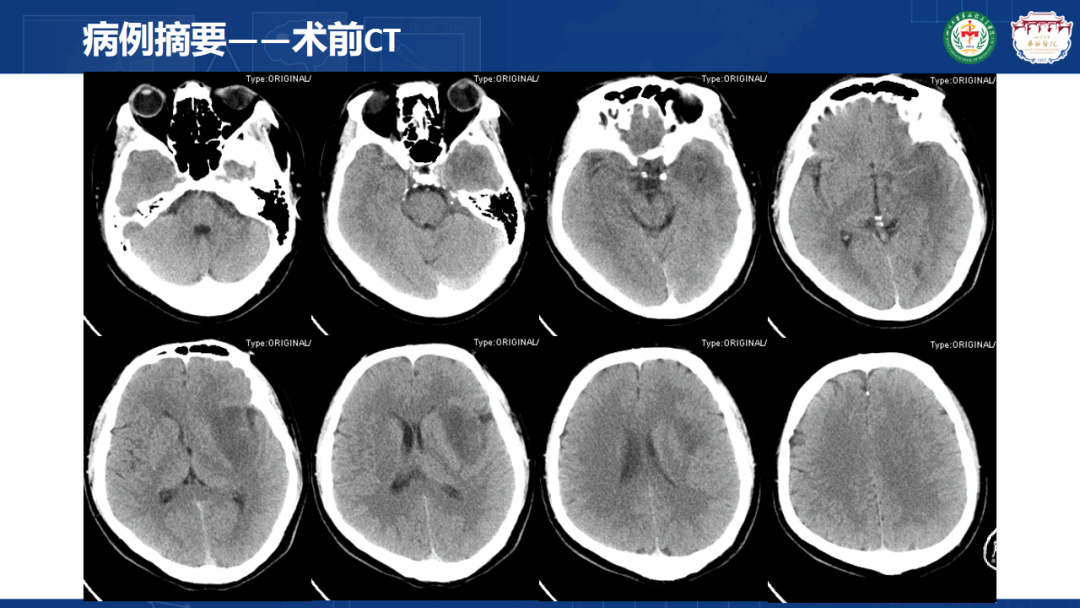

来自四川大学华西医院的曾云辉医师带来《岛叶胶质瘤手术及综合治疗》。该病例是一名41岁男性IT从业者,表现为头晕、右侧肢体麻木伴幻听,MRI显示左侧额颞岛叶占位累及海马头,DTl重建显示肿瘤包绕大脑中动脉分支。术中使用无牵拉技术联合多模态监测,经颞叶皮层造瘘切除病灶,术中重点保护侧裂静脉及M2段穿支血管。术后病理确诊为IDH突变型少突胶质细胞瘤(WHO 3级),规范实施同步放化疗联合6周期替莫唑胺辅助化疗。随访显示肿瘤控制良好,患者神经功能完整并恢复工作。